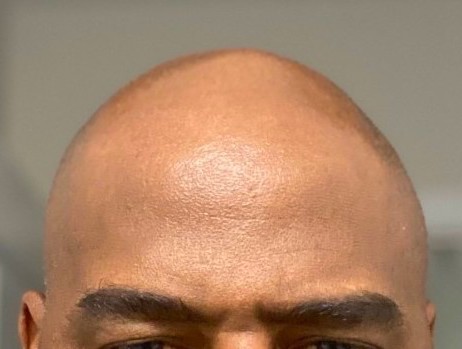

Patient 100

Desire for reshaping of an asymmetric flat back of the head in a shaved head male.

A combined back of the head reshaping procedure was done with a custom skull implant, sagittal ridge reduction and a right temporal muscle reduction.

Desire for reshaping of an asymmetric flat back of the head in a shaved head male.

A combined back of the head reshaping procedure was done with a custom skull implant, sagittal ridge reduction and a right temporal muscle reduction.